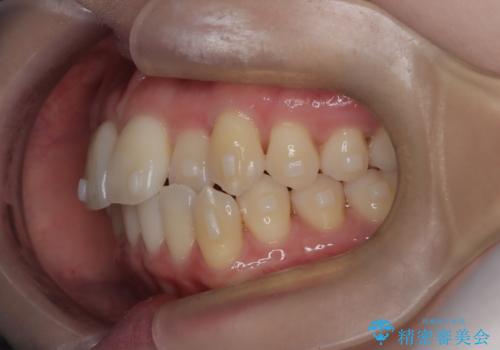

- 左上2の反対咬合(交叉咬合)をインビザラインを用いて治療しました。反対咬合は、歯列の不正咬合の一つであり、上の歯が下の歯よりも内側に位置する状態です。反対咬合は咀嚼や発音に影響を与えることがあります。

左上2の反対咬合をインビザラインで治療する際に、IPR(Interproximal Reduction)を行いました。 IPRとは、隣接する歯の間のエナメル質をわずかに削る手法で、歯の幅を減少させることによって歯列を整える技術です。